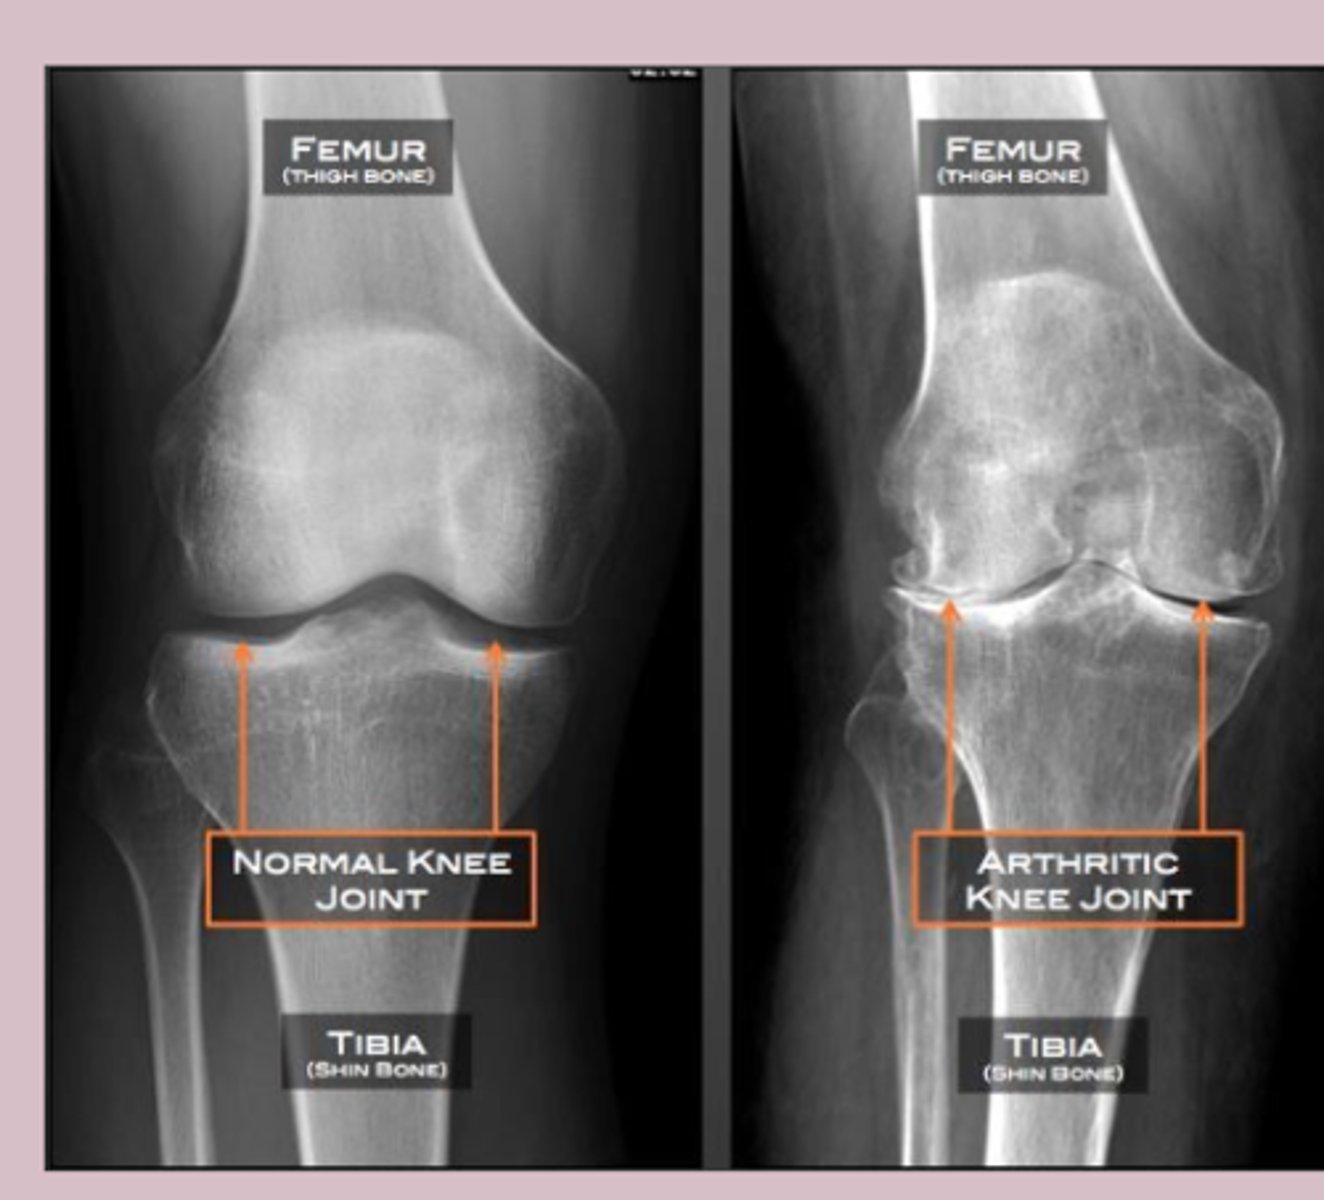

knee

knowt flashcard image